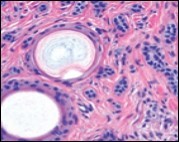

Lesions are generally superficial and infrequently invade lower dermis. Tendency for peri-neural or intra-neural infiltration, cogitated in adjunctive cutaneous carcinomas, is exceptional in desmoplastic trichoepithelioma. Nevertheless, desmoplastic trichoepithelioma can be exemplified as a component of particularly desmoplastic, cutaneous carcinomas demonstrating foci of peri-neural involvement 4, 5. Figure 1, Figure 2, Figure 3, Figure 4, Figure 5, Figure 6, Figure 7, Figure 8.

Figure 1.Desmoplastic trichoepithelioma demonstrating aggregates of basaloid cells with numerous keratinous horn cysts interspersed in an intensely fibrotic stroma 9.